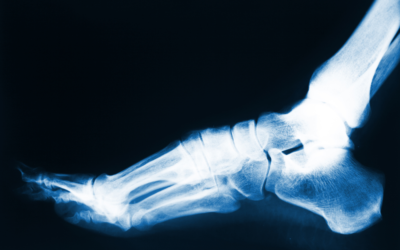

Do I Really Need Foot Surgery? Reasons Why Surgery Might Be Recommended

Most foot issues can be managed conservatively, and with non-invasive treatments but there are times when foot surgery might be recommended. For some patients, it might be necessary to correct an underlying issue that is causing foot pain or other problems.Reasons...